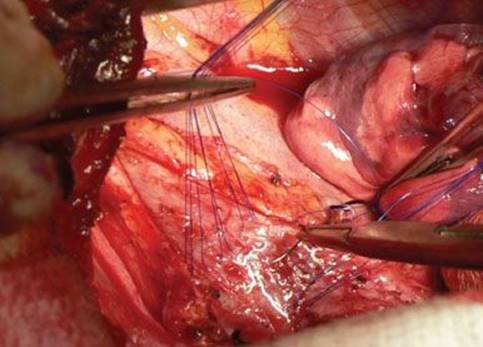

The mesh is sutured into place to splint the posterior airway walls using 4-0 polypropylene. Other groups prefer absorbable material such as polyglactin, but the longevity of polypropylene seems useful in these cases where remodeling forces may continue to exist postsurgery. The risk of mesh infection from inadvertently full-thickness sutures has not been borne out. Partial-thickness U-stitches are placed in a row across the distal trachea, a row across the bilateral mainstem bronchial origins, as well as a single suture, which is centered in the middle of this “carinal triangle” of sutures. Each row comprises four sutures. The first suture is placed through the mesh, then in mattress fashion at the cartilaginous–membranous junction of the airway, making sure that the cartilaginous ring and not simply an interspace is engaged, and then the suture is passed back up through the mesh. The next two mattress sutures are placed to gather up the laxity in the membranous tracheal wall. These gather 2 to 3 mm of posterior membrane each (Fig. 40.5). Previously these were placed one-third and then two-thirds across the width of the trachea. As a modification to further tighten the plication, the sutures are spaced in those positions in the native tracheal wall, but the placement in the mesh is moved laterally toward each edge. In this way the excess laxity of the membrane is tightened toward the cartilage–membranous junctions (Fig. 40.6). The fourth suture is a cartilaginous–membranous suture on the contralateral side.

After the distal tracheal row is placed, the right mainstem row of sutures is placed, and then a central membranous wall suture is usually placed before the left mainstem row is performed. Sutures are managed by ordering them using hemostats to avoid tangling. The mesh is then parachuted into place and then the sutures are tied, with the cartilaginous sutures tied first, then the membranous wall sutures, to avoid avulsing the sutures from the less substantial membranous wall tissue.

Figure 40.5 Suture placement at the carina. Distal tracheal and right mainstem bronchial rows are completed. Central triangle suture is being placed.